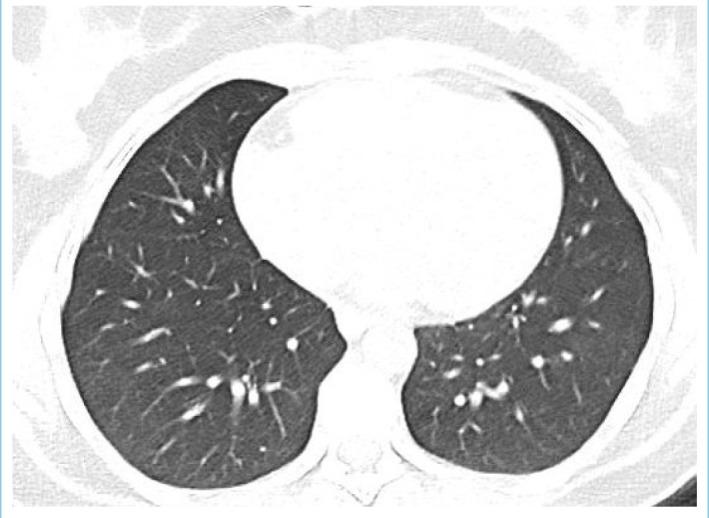

Numerous neurological manifestations associated with COVID-19 have been reported. However, abducens nerve palsy (ANP) associated with COVID-19 is very rare and mostly related to accompanying respiratory symptoms. Here we present a 29-year-old woman with unilateral ANP manifesting with diplopia and positive SARS-CoV-2 S antibodies, which were checked later. On admission, she had signs of viral pneumonia in thorax CT without any respiratory symptoms. Her cranial neuroimaging revealed no abnormality. Following treatment with favipiravir 2x1600 mg loading dose and then 2x600mg daily maintenance, dexamethasone 8 mg/day and enoxaparin 6000 IU/day, her CT findings recovered completely whereas her ANP only partially resolved. One week after the end of COVID-19 treatment, she also developed Herpes simplex keratitis which was successfully treated with valacyclovir. It should be kept in mind that isolated abducens nerve palsy may be the only finding of COVID-19 cases without any respiratory symptoms.

已有许多与新冠病毒病(COVID-19)相关的神经学表现的报道。然而,与COVID-19相关的外展神经麻痹(ANP)非常罕见,且大多与伴随的呼吸道症状有关。在此,我们报告一名29岁女性,出现单侧ANP,表现为复视,后来检测出严重急性呼吸综合征冠状病毒2(SARS-CoV-2)S抗体呈阳性。入院时,她胸部CT有病毒性肺炎迹象,但无任何呼吸道症状。她的头颅神经影像学检查未发现异常。在用法匹拉韦2×1600mg负荷剂量,然后每日2×600mg维持剂量、地塞米松8mg/天和依诺肝素6000IU/天治疗后,她的CT表现完全恢复,而她的ANP仅部分缓解。COVID-19治疗结束一周后,她还患上了单纯疱疹性角膜炎,用伐昔洛韦成功治疗。应记住,孤立的外展神经麻痹可能是无任何呼吸道症状的COVID-19病例的唯一表现。